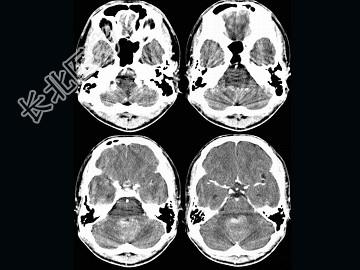

- 单项选择题男,16岁, 头痛、呕吐10天,CT检查, 最可能的诊断为 ( )

A、脑膜瘤

B、髓母细胞瘤

C、室管膜瘤

D、脑血管瘤

E、血管母细胞瘤